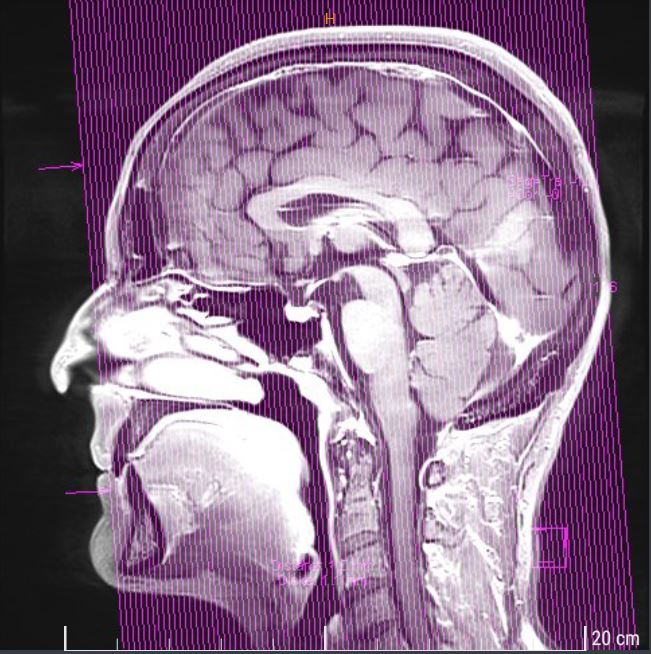

Da ich seit einiger Zeit manchmal Wortfindungsstörungen habe, und sich meine Kinder schon das ein oder andere Mal darüber lustig gemacht hatten, ist für mich nun klar, dass das wohl mit der Krebserkrankung in Zusammenhang liegt. Sind da bereits Metastasen im Gehirn? Könnte ich noch einen Gehirntumor haben!???

Alex und unsere Tochter begleiten mich. Die Nadel für das Kontrastmittel in meiner rechten Hand schmerzt. Dann werde ich zur Magnetresonanztomographie, kurz MRT, in die Röhre gefahren. Ich schließe die Augen und muss fast über die seltsamen Töne und Geräusche lachen, die die Apparatur da von sich gibt.

Dann erscheint eine Ärztin und frägt nach mir. Ich torkle ihr hinterher. Also… sie hat nichts Auffälliges in meinem Schädel entdecken können. Mein Gehirn sei ohne Befund!